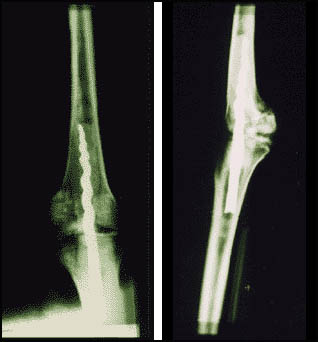

Nell'agosto 1995, il Dr. Wilfred Griggs guidò un team di ricercatori della Brigham Young University, che stavano conducendo la ricerca del DNA su sei mummie del Museo. Durante la ricerca, una radiografia rivelò un perno di metallo nella gamba sinistra di Usermontu. In un primo momento il dottor Griggs pensò che la vite "dovesse essere un recente tentativo di riparare la mummia, forse non più di 100 anni fa. Quando l'abbiamo vista ai raggi X nel mese di agosto, ho pensato che non avevo mai visto qualcosa di simile, fatto in epoca moderna. Non mi è venuto in mente in quel momento che ci potesse essere nulla di questo tipo d'intervento fatto in epoca antica ". continua Griggs.

Così, affascinato dalle possibilità di questa scoperta, nel novembre il Dr. Griggs ritornò al Museo, una sera, a dare un'occhiata più da vicino. Dopo circa 30 minuti di osservazione da vicino della gamba, il Dr. Griggs si convinse che il perno fosse molto più vecchio di quanto lui previsto, ed era così eccitato che pensò valesse la pena di un'ulteriore indagine su scala reale.

L'8 febbraio 1996, il Dr. Griggs ritornò con specialisti per determinare se questo fosse il primo tentativo di intervento chirurgico al ginocchio antico mai scoperto. E con nostra sorpresa, non vi è alcun dubbio che si tratti sicuramente di un'operazione antica. Mai prima d'ora una mummia egizia aveva mostrato una tale caratteristica.

Fino ad oggi, sappiamo che la composizione metallica del perno a vite è costituit< da ferro puro, e che è stato messo prima che Usermontu fosse mummificato. Ciò corrisponde con il periodo di tempo accettato per la vita di Usermontu (ca. 630 a.C.) durante l'età del ferro in Egitto.

Non solo i ricercatori sistupirono che il perno potesse essere antico, ma anche che il suo disegno fosse di tipo molto avanzato, dal punto divista dei chirurghi in visita.

"Il perno è simile ai progetti stessi che usiamo oggi per ottenere una buona stabilizzazione delle ossa", ha dichiarato il Dr. Richard Jackson, chirurgo ortopedico del BYU.

A quanto pare, gli antichi sapevano come usare le flange su una vite per stabilizzare la rotazione della gamba.